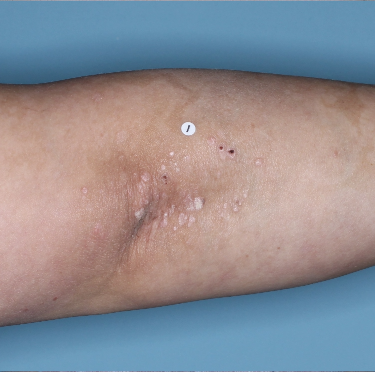

48% of patients were completely clear* at Week 481

Week 0

PASI=20.1

Week 16

PASI=0

(100% PASI

improvement)

Week 48

PASI=0

(100% PASI

improvement)

Individual results may vary.

Images are Janssen-owned from blinded trial: NCT05272150.